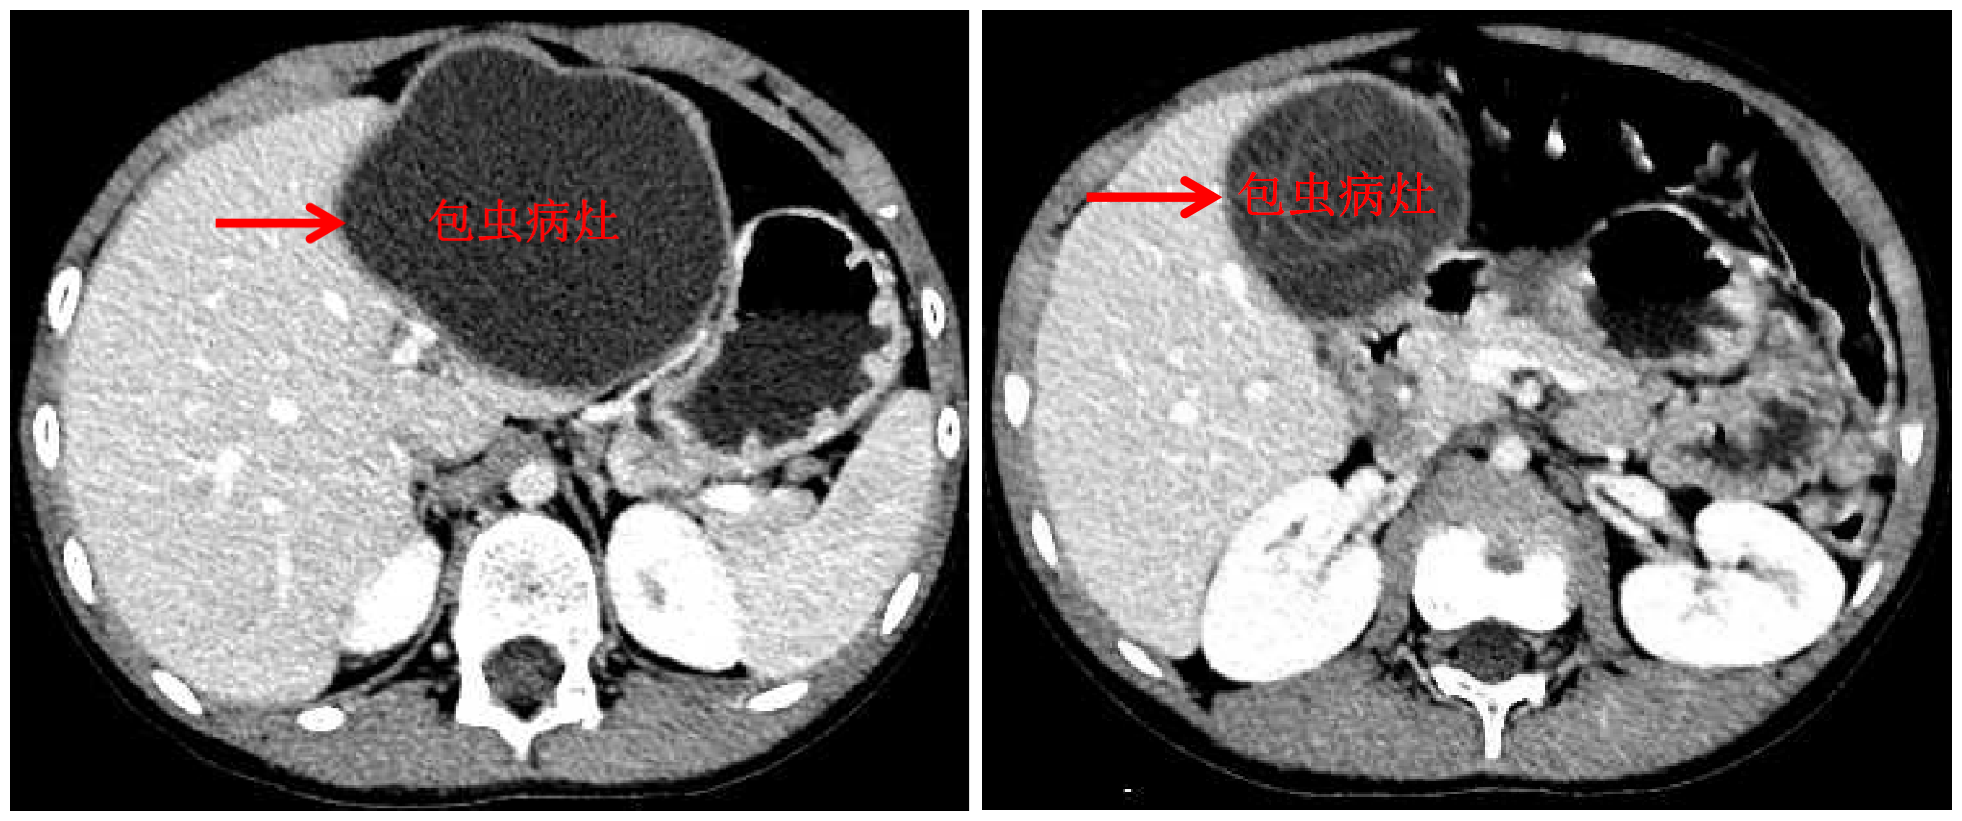

清华新闻网10月13日电 国庆前,8岁的小扎西被父亲带到了西藏大学附属拉萨市人民医院普外科,此次距离孩子确诊肝包虫病已有一年之久。腹部影像显示,小扎西体内的囊型肝包虫病已经侵袭了左肝大部。

包虫病灶